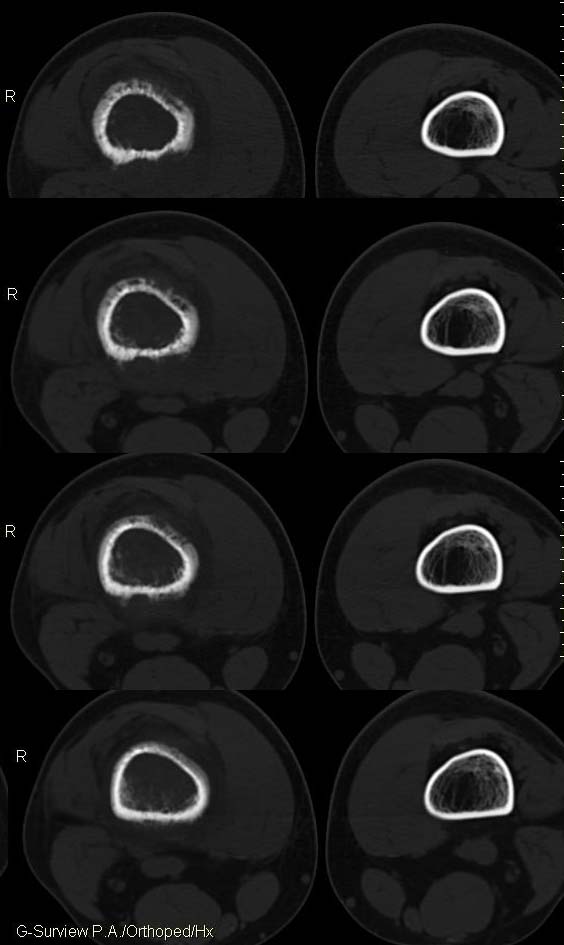

20岁,男,右股骨下端疼痛一个月,无发热,白细胞正常,皮肤不红,肿胀,触痛。

骨膜针状反应,是尤文氏骨肉瘤的典型表现!

右股骨下端很长范围内的髓腔扩大,骨小梁破坏消失,皮质亦呈融骨性破坏,周围脂肪层次紊乱,肌肉受累及密度减低。考虑为:恶性骨肿瘤。请专家们分析骨肉瘤及尤文氏肉瘤的ct征象。

6.ct及mri:能较好地判断肿瘤的范围及侵犯软组织的情况。mri可见瘤体处广泛性骨质破坏,呈软组织肿块影;在t1加权像上呈均匀的长t1信号;在t2加权像上呈很长t2高信号。在ct上显示为源于骨组织的软组织肿块,骨质广泛破坏。

此病例基本可定是恶性骨肿瘤:髓腔内长范围肿块、皮质不规则破坏、软块及软组织浸润、瘤骨及不规则骨膜反应等。可以肯定地除外炎性病变和骨纤。

结合临床还是将尤文氏肉瘤放在前面,骨肉瘤不排除。纤维肉瘤及恶纤组多见老年人,不放在首要诊断范围内。